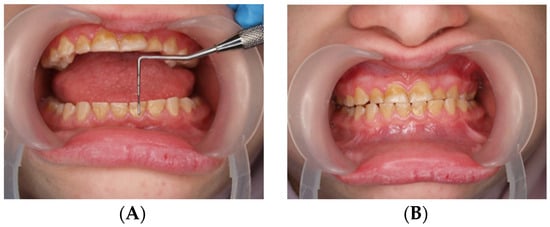

Figure 1.

(A,B) Resting position of the lower jaw.